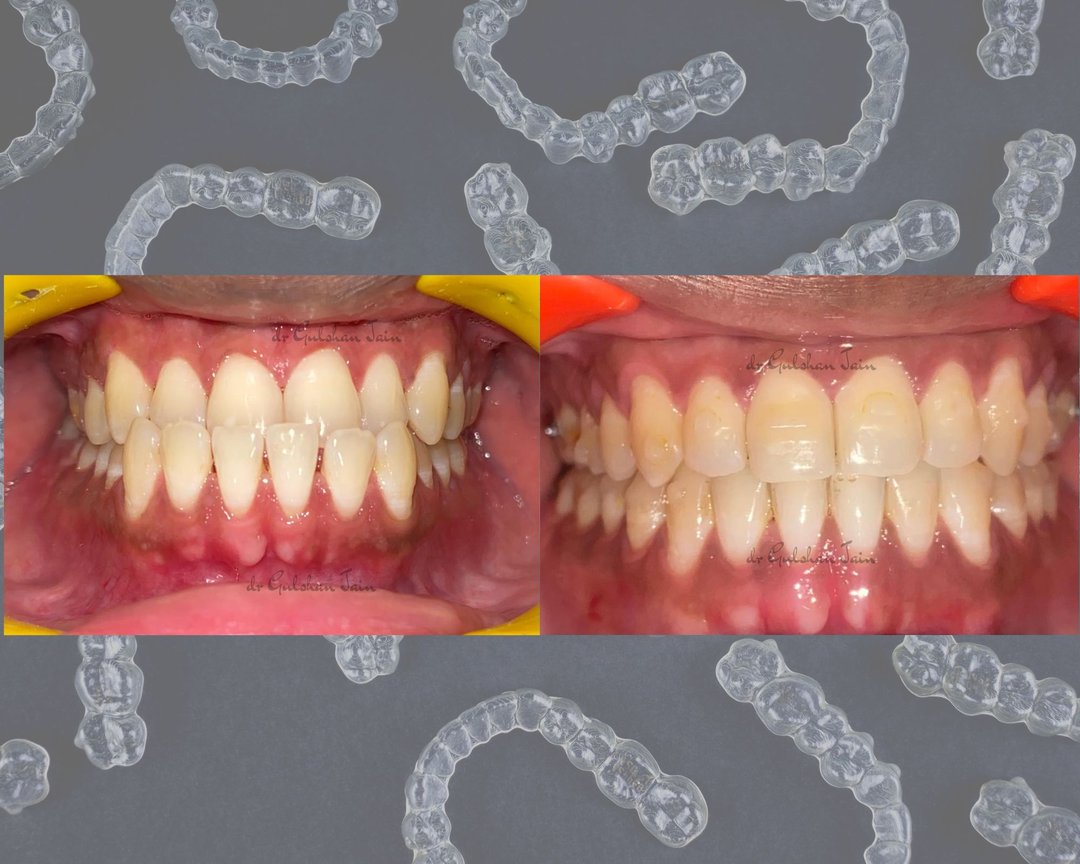

Welcome to our gallery

See how our company transforms ideas into reality. This gallery is a visual testament to our work and achievements.